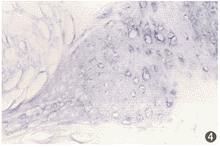

图4 舌粘膜上皮鳞癌,癌巢中基本上见不到RAR β mRNA阳性细胞(ISH ×400)

RAR β mRNA在口腔癌发生发展过程中的表达(表1)。 RAR β mRNA主要分布于正常舌粘膜上皮基底层及基底上3~4层细胞胞浆中(图1),随上皮恶变进展,RAR β mRNA表达自基底上层向下逐渐消失(图2~4)。正常粘膜、单纯性增生、轻中度异常增生、重度异常增生、原位癌、鳞癌的RAR β mRNA阳性率分别为100.0%、87.5%、75.0%、72.2%、45.5%和18.8%,即随口腔癌变进展,RAR β mRNA表达递减;特别是当进入鳞癌阶段,癌细胞中基本上见不到RAR β mRNA阳性细胞;与正常粘膜(含单纯增生)和癌前病变(异常增生)阳性率相比,口腔癌(含原位癌)差异有显著性(P<0.01)。